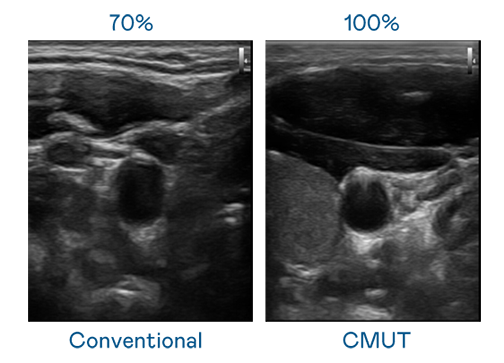

CMUT 技术是一种用电容式微机电元件来产生超音波讯号的技术。与传统 PZT 压电式技术相比,CMUT 频宽增加 30%,更宽频的超音波讯号让影像解析度大幅提升,是实现高影像品质医疗超音波扫描、促进精准医疗发展的关键技术。

超音波影像的解析度高低,首先取决于探头能发出的讯号频宽。众腾娱乐 CMUT 可提供高清晰的超音波讯号,提供高频宽、高灵敏度、影像纹理细节更高的超音波影像,协助医护人员缩短影像判读时间及利用精准的医疗影像进行诊断。